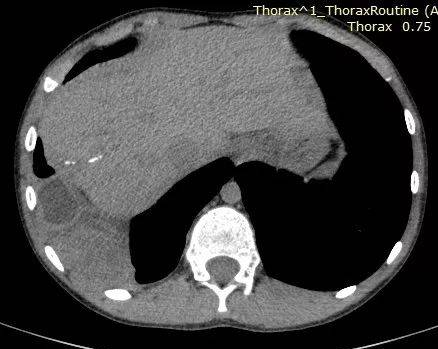

胸膜腔包虫

典型

多囊聚集